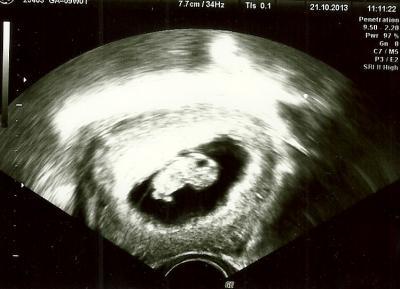

Hallo ihr Lieben! Ich konnte die vergangene Nacht kaum schlafen, habe mich von der einen Seite zur anderen gedreht. Seit ein paar Tagen hat die Spannung meiner Brüste nachgelassen. Ich war fast am verzweifeln. Ist meine Schwangerschaft beendet???? Dr.Google gab noch seinen Rest dazu, ich war fertig. Ich ging also zum Arzt (erster Ultraschalltermin) und war so sehr glücklich, das kleine Mini-Baby zu sehen (2,2cm, 8w+5). Und die kleinen süßen Beinchen. Das Herzchen pocht wild. Hach, ich könnte nur schwärmen. Die Schwester hat mir dazu noch dringend abzuraten, bei Fragen nicht bei Google zu googlen !!! Ich atme also auf und werde meinen Eltern heute von der Freude berichten. Ich fall` fast vom Stuhl...weil ich so aufgeregt bin, versteht sich!!! Liebste Grüße

Bild zu Zurück vom Arzt - Forum für Mai - Mamis

Huhu Das ist toll das alles ok ist! Ich zitter immer mit allen mit und freue mich über die Arztberichte. Besonders toll die mit süßen Fotos anbei. Das ist echt toll von dir, mit diesen kleinen Füßen dran Bei mir ist zur Zeit nur eine Kugel zu erkennen. Aber am Donnerstag kommt hoffentlich ein besseres:-) LG Daniela